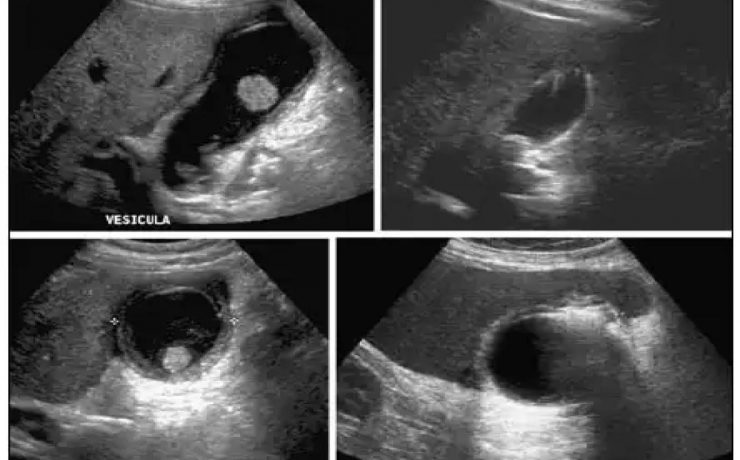

El cólico nefrítico se define como un dolor agudo en el flanco (en ocasiones se irradia a la ingle) escrito por los pacientes como el peor de su vida y que generalmente se acompaña de náuseas, vómitos y hematuria. La litiasis es un agregado policristalino compuesto de cristaloides (95%) y